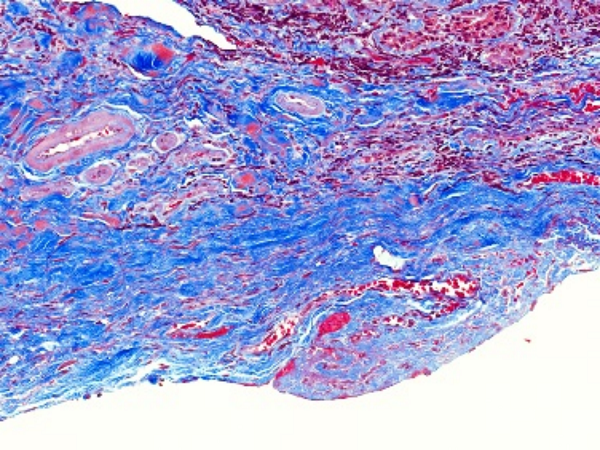

Masson染色是一种用于显示组织中纤维成分的特殊染色方法,主要用于区分胶原纤维和肌纤维,在病理学和组织学研究中有广泛的应用。**一、染色原理**1. 试剂作用 - **酸性复红**:它是一种酸性染料,能够将细胞质、肌纤维等染成红色。在染色过程中,酸性复红与肌纤维中的碱性蛋白结合,使肌纤维呈现出红

400-6863-882 立即咨询Masson染色是一种用于显示组织中纤维成分的特殊染色方法,主要用于区分胶原纤维和肌纤维,在病理学和组织学研究中有广泛的应用。

**四、结果观察与分析**

2. 肌纤维

- 被酸性复红染色后呈红色,通过观察肌纤维的分布、走向和形态,可以了解肌肉组织的结构和功能。例如,在心肌组织中,心肌纤维呈分支状,相互连接成网状;在平滑肌组织中,肌纤维呈长梭形,排列较为规则。

3. 胶原纤维

- 被苯胺蓝染色后呈蓝色。可以观察胶原纤维在组织中的分布和含量,这对于研究组织的纤维化程度、创伤修复等过程具有重要意义。例如,在肝脏纤维化的组织中,会出现大量蓝色的胶原纤维增生。